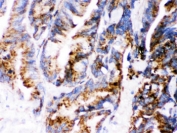

IHC testing of FFPE human intestinal cancer wtih Cathepsin D antibody. HIER: Boil the paraffin sections in pH 6, 10mM citrate buffer for 20 minutes and allow to cool prior to staining.